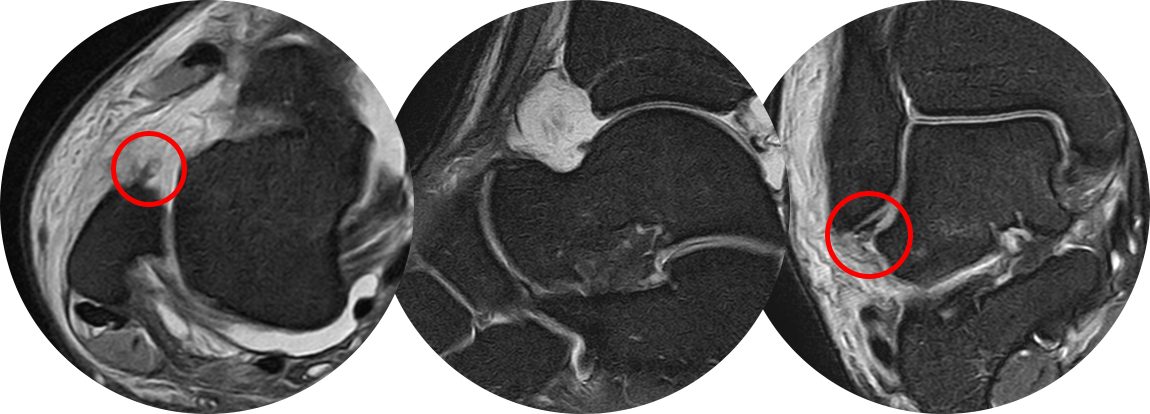

수술 후 MRI 사진으로

좌측 사진에서 외측 복사뼈 부착 부위에서 완전 떨어졌던 전거비인대가 잘 봉합되어 있는 것을 볼 수 있고,

우측 사진을 통해 최소 절개를 통한 2개의 앵커 삽입을 통해 뼈에 인대를 넓게 부착을 시켜준 것이 확인됩니다.